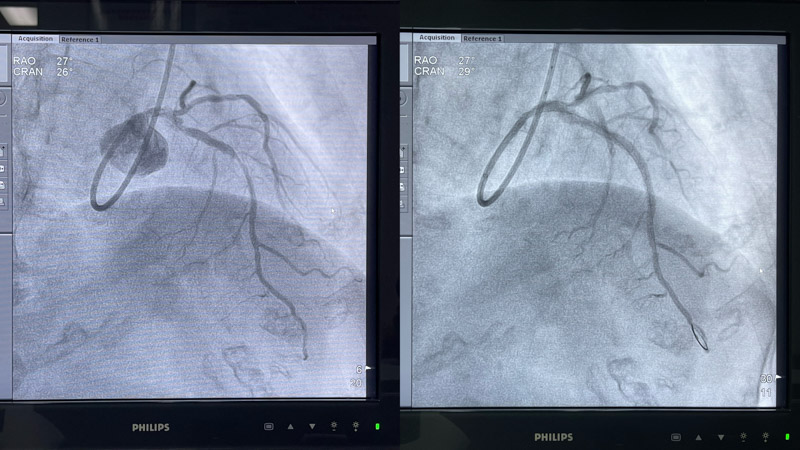

術(shù)中,心血管內(nèi)科介入團(tuán)隊將Shockwave C2 IVL 3.0*12mm 震波球囊置入前降支病變處,以4-6atm進(jìn)行擴(kuò)張后觸發(fā)8次10秒沖擊波,實施鈣化斑塊碎裂術(shù),術(shù)后支架膨脹不全處明顯擴(kuò)張,并順利于前降支近中段植入1枚支架。復(fù)查IVUS可見鈣化斑塊碎裂,支架貼壁和膨脹良好,血管擴(kuò)張成形滿意,術(shù)后患者胸痛癥狀明顯好轉(zhuǎn)。

▲ 震波前、后造影對比圖